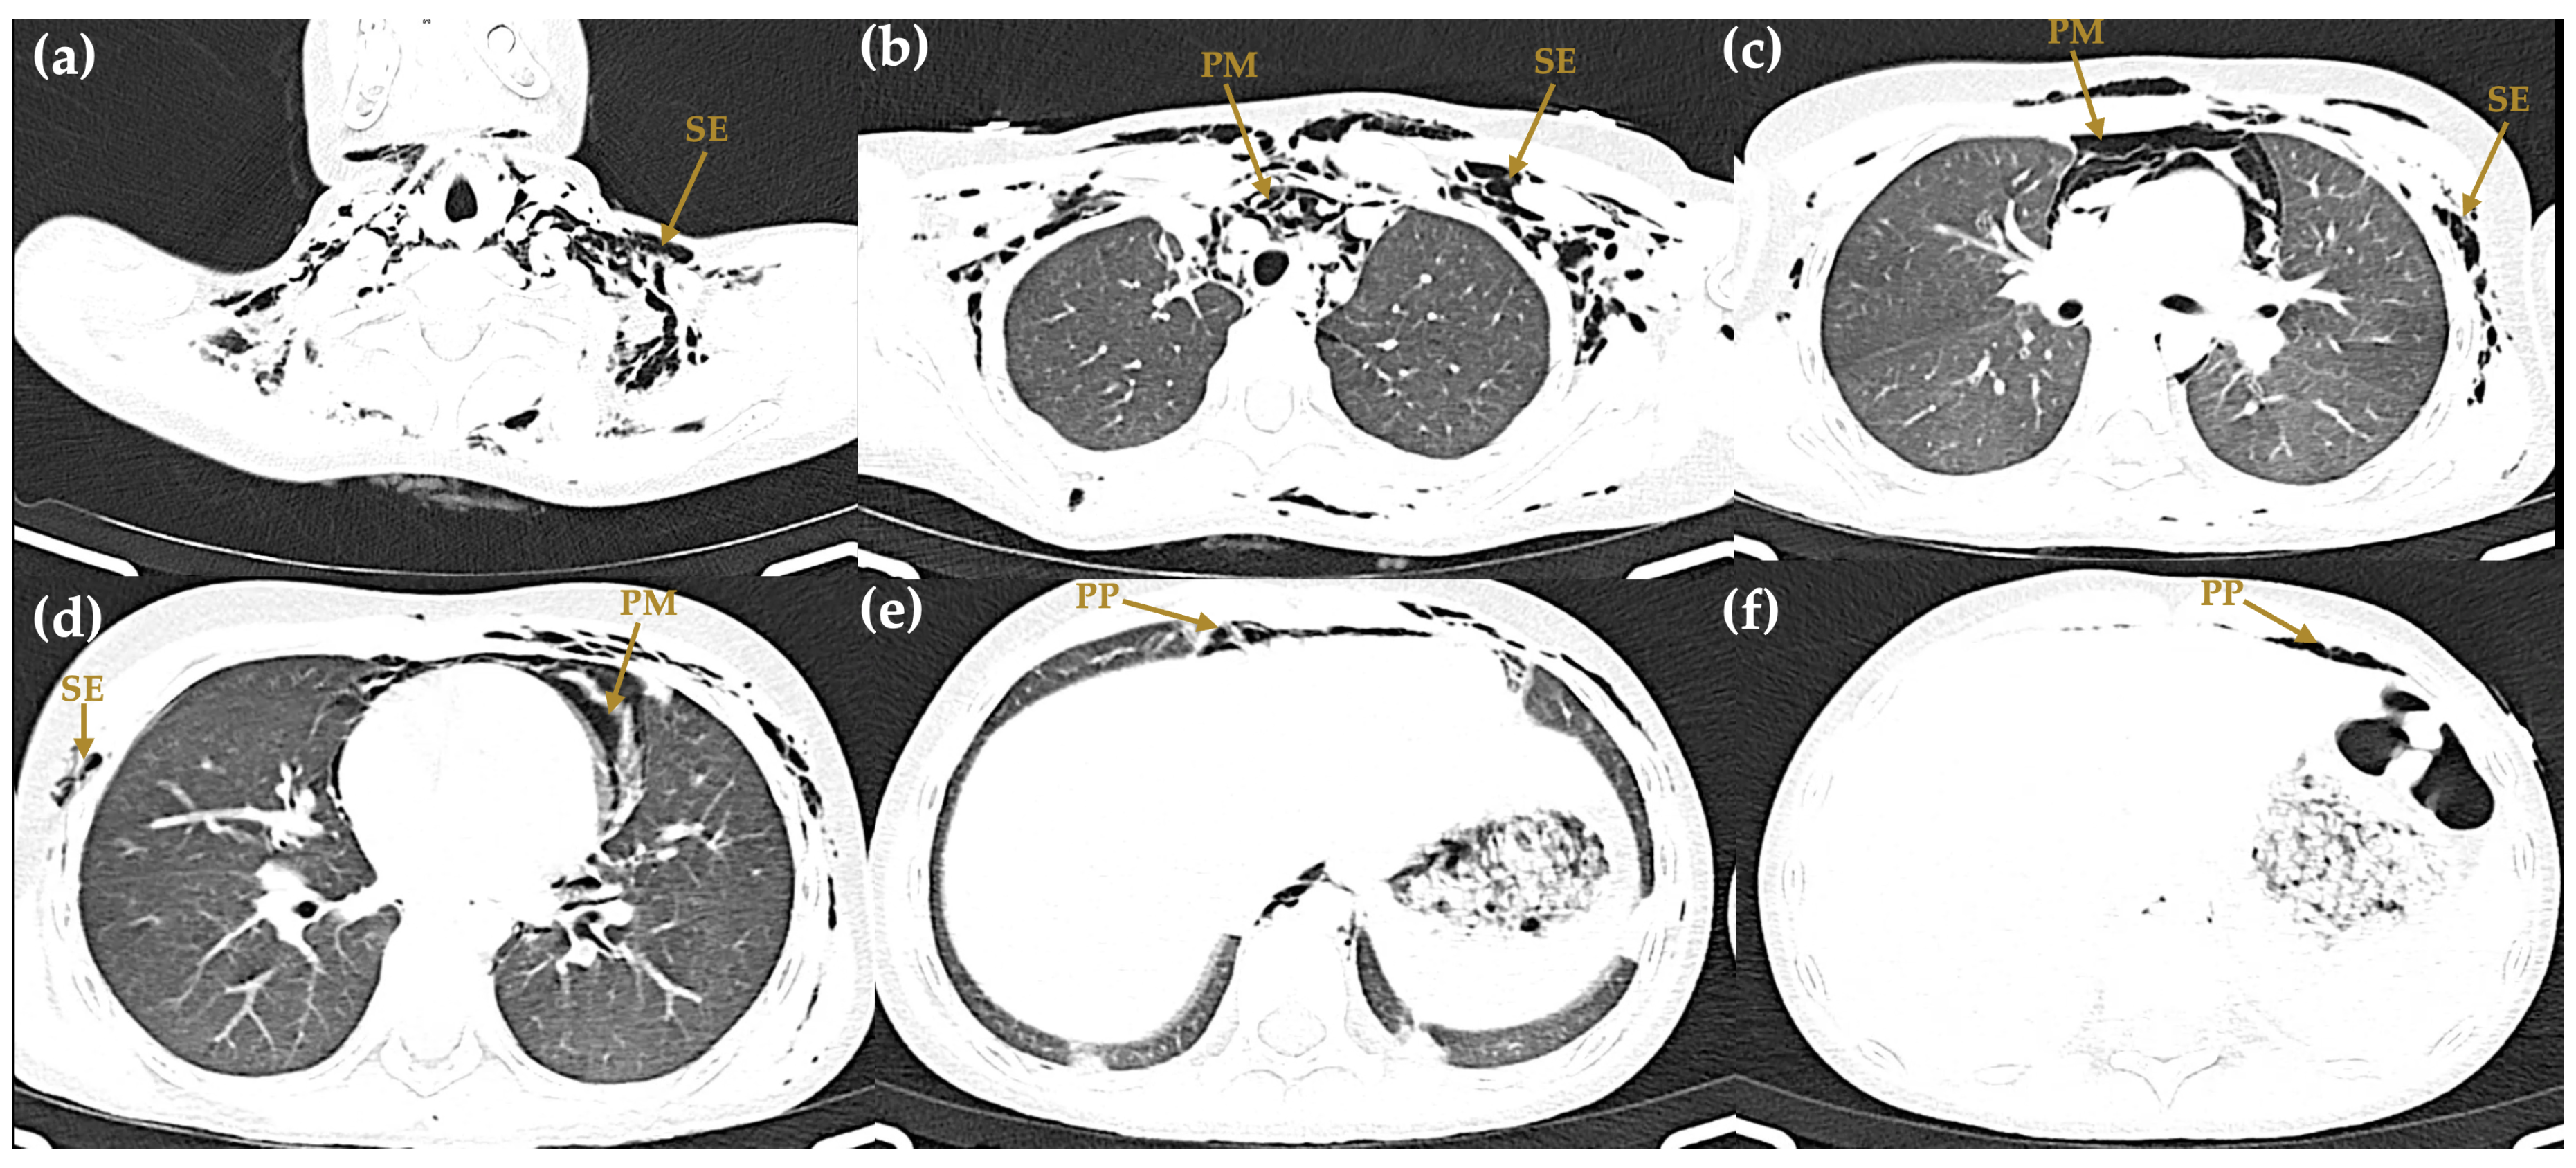

The initial chest radiograph demonstrated pneumomediastinum and extensive subcutaneous emphysema extending from the skull base to the mid-thorax, with a central trachea and normal pulmonary parenchyma (Figure 1). On hospital day 2, computed tomography (CT) of the chest confirmed pneumomediastinum with air dissecting along the esophagus, trachea, and pericardium, as well as a left-sided pneumothorax, pneumoperitoneum, and subcutaneous emphysema extending through the cervical, shoulder, and pectoral musculature (Figure 4).

Figure 4. Axial computed tomography of the chest and abdomen (hospital day 2). (a) Cervical level (lung window) showing subcutaneous emphysema (SE) dissecting through the deep cervical soft tissues. (b) Upper thorax (lung window) demonstrating pneumomediastinum (PM) with air surrounding the great vessels, and bilateral subcutaneous emphysema (SE) in the pectoral musculature. (c) Mid-thorax (lung window) confirming extensive pneumomediastinum (PM) and subcutaneous emphysema (SE). (d) Lower thorax (lung window) showing persistent pneumomediastinum (PM) and subcutaneous emphysema (SE) at the level of the pulmonary hila. (e) Upper abdomen (soft-tissue window) revealing pneumoperitoneum (PP) as free air anterior to the liver. (f) Upper abdomen (soft-tissue window) with additional evidence of pneumoperitoneum (PP) and residual air dissection.